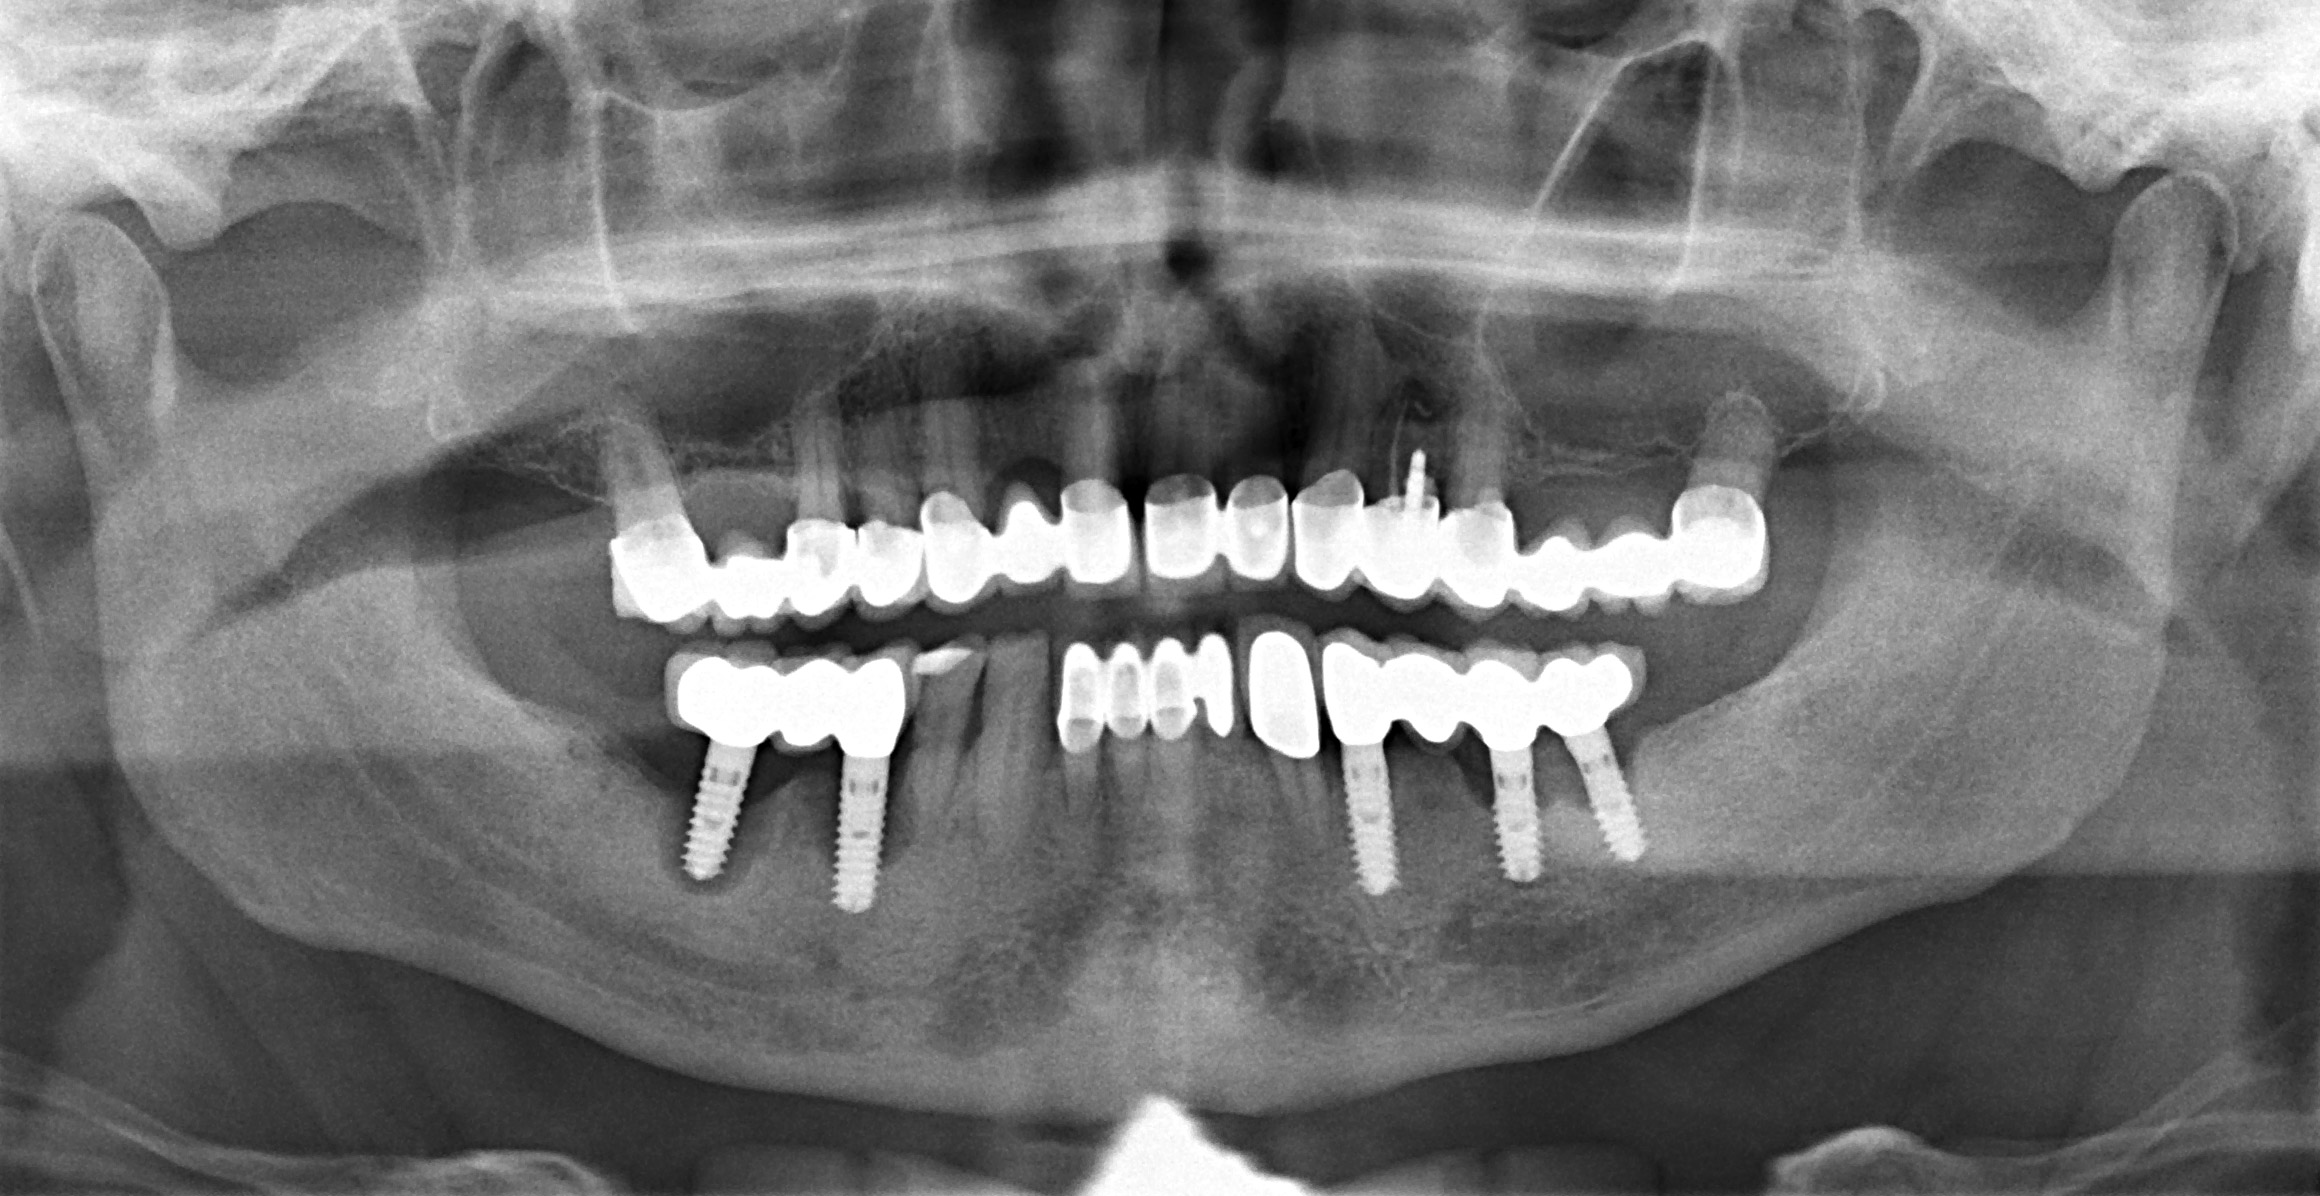

Periimplantitisbehandlung

Knochenabbau am Implantat verhindern

Zu den häufigen Komplikationen nach dem Einsetzen von Implantaten zählen unbemerkte Entzündungen des Weichgewebes am Implantat. Rechtzeitig erkannt und behandelt klingen sie meist problemlos wieder ab. Unbehandelt können sich diese Infektionen bis auf den Knochen ausdehnen und dort irreversible Schäden anrichten. Der Knochenabbau kann schlimmstenfalls zum Verlust des Implantats führen.